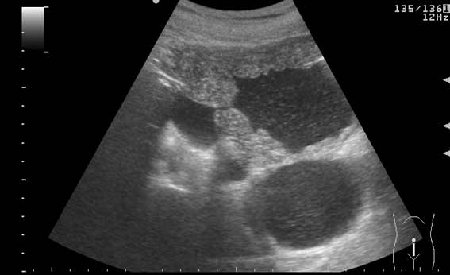

УЗИ мочевого пузыря у пожилого мужчины выявлены следующие изменения.

Signs of chronic urinary retention; evident thickening of the urinary bladder mucosa; large diverticulas. Residual volume evlaluation required; full prostatic assessment is recommended.

неравномерное утолщение стенок мочевого пузыря,признаки застоя в мочевом пузыре,расширенные дистальные отделы мочеточников,на первом снимке-дивертикул?слева,уввеличенная отечная простата

Все верно, за исключением того что простаты на картинках нет. Здорово, что Вы заметили расширение мочеточников. Есть также воздух в МП после цистоскопии.

если не поздно с ответами то мое мнение, что это гыпертрофия слизистой мочевого пузыря с разширеными мочеточниками и одним дивертикулом как правило такие изменения на фоне большой аденомы и у меня был случай таких же изменений на фоне фимоза у взрослого музчины правда на фоне еще и умственной отсталости